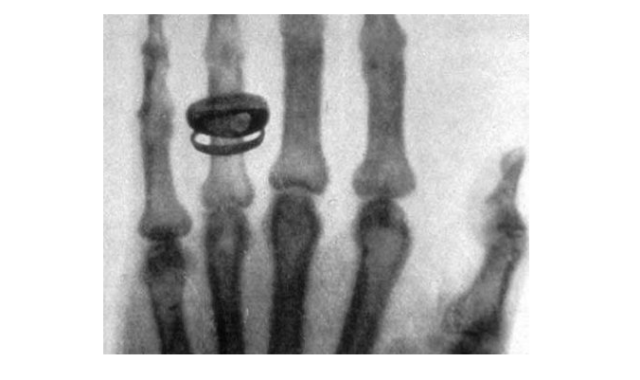

Последнее свойство было обнаружено случайно. Рука экспериментатора оказалась между катодной трубкой и экраном, на экране появилась ее тень, на которой были видны не только внешние очертания кисти, но и очертания костей. Появилась возможность получать снимки внутренних органов без хирургического вмешательства. Первым рентгеновским снимком в истории был снимок кисти руки жены В. Рентгена, Анны-Берты, с кольцом на пальце.

Рис. 2. Первый рентгеновский снимок руки с кольцом.